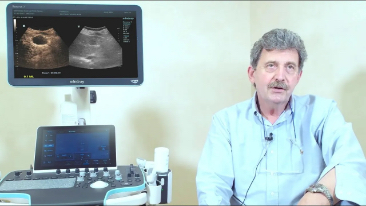

Resona 7

Mindray? ??? ??? ?? ??? ???? ??? ?? ??? ??? ????? ??? ????. ?? ???? ZONE Sonography? ??? ???? ?? Resona 7? ??? ZST+ ???? ?? ?? ? ?? ??? ????? ?? ??? ??? ??? ? ?? ????.

?? Resona 7? ???? ??? ?? ???? ??? ??? ???? ??? ?? ???? V Flow? ?? CNS ??? ?? 3D ??? ???? ?? ???? ?? ??? ?? ?? ?? ??? ??????. ???? ??? ??? ?? ?? ??? ??? ?? ?? ??? ??? Resona 7? ??? ???? ???? ??? ??? ??? ????.